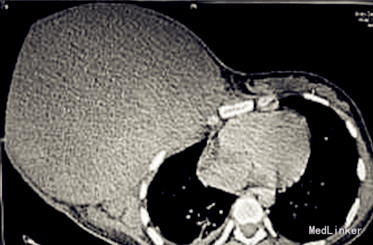

查体:生命体征平稳,患者右乳巨大肿块,长径约30 cm;皮肤水肿、微红,皮下血管怒张;肿块外下方因肿瘤溃破出血已用碘方纱填压止血。 辅查:胸CT提示右第3、4前肋骨皮质不连续,考虑肿瘤侵犯,右胸少量积液。穿刺活检考虑恶性叶状肿瘤。

诊断:右侧乳房肿物性质待查 治疗:完整切除肿瘤,基底肉眼干净。术中发现右第3、4肋骨断裂、内陷,并非肿瘤侵犯而是肿瘤过大、过重所致骨折。术后病理:肿瘤重5.5 kg,解剖标本见肿块主要为实质性,灰白色,其中可见多个小囊腔,腔内有咖啡色和淡黄色液,临床酷似叶状肿瘤。但结合多项免疫组化结果及免疫荧光原位杂交(FISH)检测SS18基因易位为阴性结果,最终诊断为纤维肉瘤。